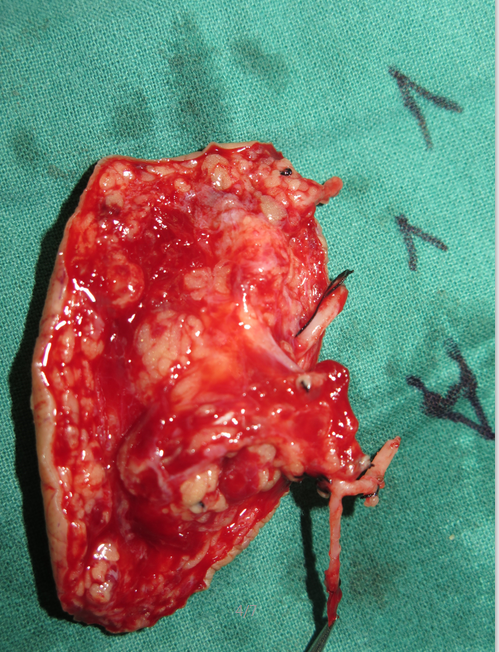

补充8月10日值班的游离足内侧皮瓣修复并桥接血管

QQ截图20160817190730.png QQ截图20160817190742.png QQ截图20160817190753.png QQ截图20160817190810.png QQ截图20160817190821.png QQ截图20160817191358.png QQ截图20160817191412.png QQ截图20160817190833.png QQ截图20160817190859.png